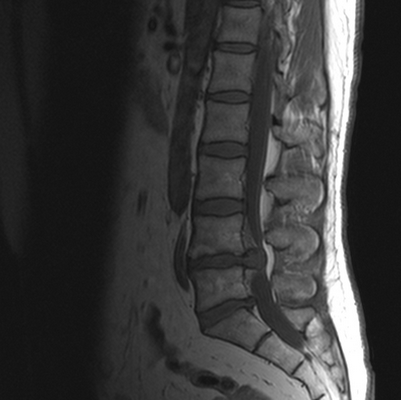

МРТ позвоночника. Сагиттальная Т2-взвешенная МРТ, срединный срез поясничного отдела. Показана нумерация позвонков, измерения позвоночного канала (черная линия). Т- дуральный мешок с ярким ликвором. L- желтая связка. Sacrum - крестец. D - межпозвоночный диск. Голубым выделен остистый отросток, желтым - тело позвонка, Голубые точки - ход корешков.

После того, как появилась ясность в способе получения МРТ изображений позвоночника, надо понять какие анатомические структуры видны. Счет позвонков ведется разными способами - сверху от зубовидного отростка С2 (осевой позвонок), от бифуркации трахеи Т5 ( пятый грудной, с погрешностью на 1 позвонок) или снизу от L5 (последний поясничный), также не исключена погрешность на 1 позвонок в связи люмбализацией или сакрализацией. Анатомия позвоночника в МРТ изображении представлена в нашей другой статье. На серии сагиттальных Т2-взвешенных МРТ позвоночника видны асе основные структуры, причем удается проследить ход корешков конского хвоста. В поясничном отделе он идет под углом вниз и выходит через межпозвоночное отверстие нижележащего позвонка. Аксиальные (поперечные) МРТ срезы всегда делаются вдоль межпозвоночного диска, то есть с учетом нормальных или патологических изгибов позвоночника. Они наиболее удобны для оценки состояния дугоотростчатых суставов. При МРТ позвоночника в поперечной плоскости МРТ срезы часто делают на разных уровнях для лучшей визуализации состояния корешков по их ходу - в дуральном мешке, затем боковом кармане дурального мешка, далее в межпозвоночном отверстии и, наконец, после выхода из него. Таким образом, в поперечном МРТ срезе позвоночника через межпозвоночное отверстие на поясничном уровне можно видеть отрезки сразу двух корешков - вышележащего на выходе из отверстия, и нижележащего в боковом кармане.